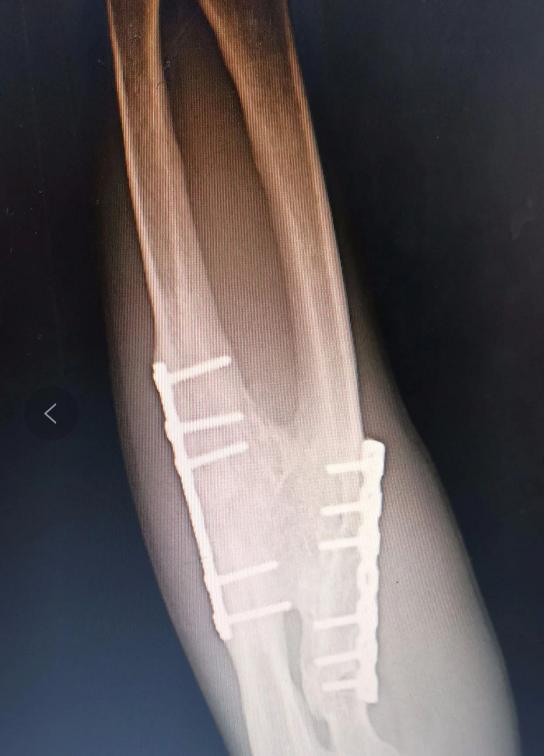

X线片分享:尺骨、桡骨骨折术后融合在一起

尺桡骨融合手术是一种针对先天性尺桡骨融合畸形的矫正手术。这种畸形会导致前臂固定在旋前位,严重影响患者的生活质量。近日,一则关于尺桡骨融合手术的X线片分享引起了医学界的关注,让我们深入了解这项技术。

尽管存在风险,尺桡骨融合手术仍然为患者带来了显著的益处。一项研究报道,一位19岁的患者接受了左侧尺桡骨融合部旋转截骨术。术前他的左前臂旋前畸形达80°,严重影响日常生活。手术后,他的左前臂旋转固定在中立位,无骨筋膜室综合征及骨间背神经损伤等并发症发生。术后1年复查时,截骨处尺骨对位对线良好,骨折线消失,已达骨性愈合。通过肩关节的内收及外旋代偿,他能够满足端碗、键盘打字等日常生活需要。